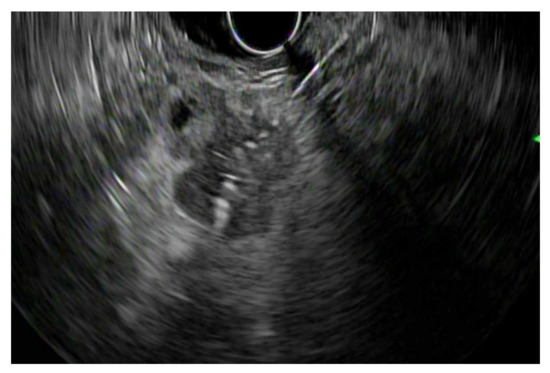

4.4. Palliation for Source Control: EUS-RFA

4.5. Palliation for Abdominal Pain: Celiac Neurolysis